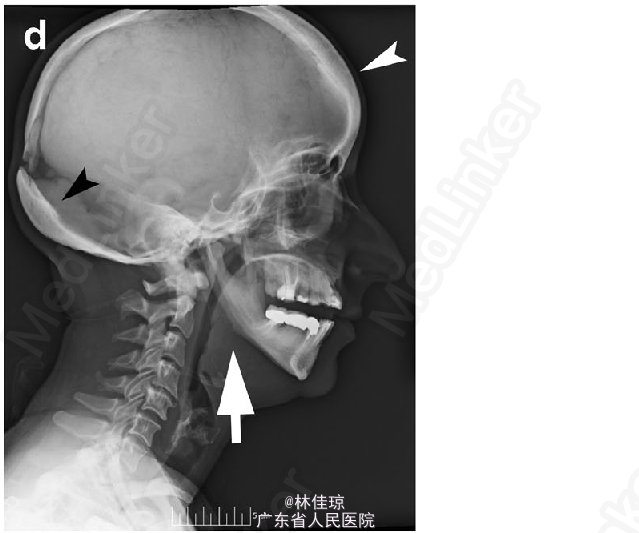

36 岁女性,妊娠 29 周,因左侧下肢轻微外伤后不能走路就诊。既往史:本次入院前左下肢持续性疼痛 1 月余。青少年初期诊断为致密性成骨不全,下肢既往疲劳性骨折史。无相似骨骼疾病家族史。

体格检查:颅面畸形、小颌畸形、手部短宽、身材矮小。腹部大小与妊娠周数相符,左下肢明显缩短、外旋畸形,皮肤完整,神经血管功能检查正常。 X 线提示股骨干横向骨折、皮质增厚,对侧股骨皮质增厚和外侧骨裂,提示可能发生骨折。